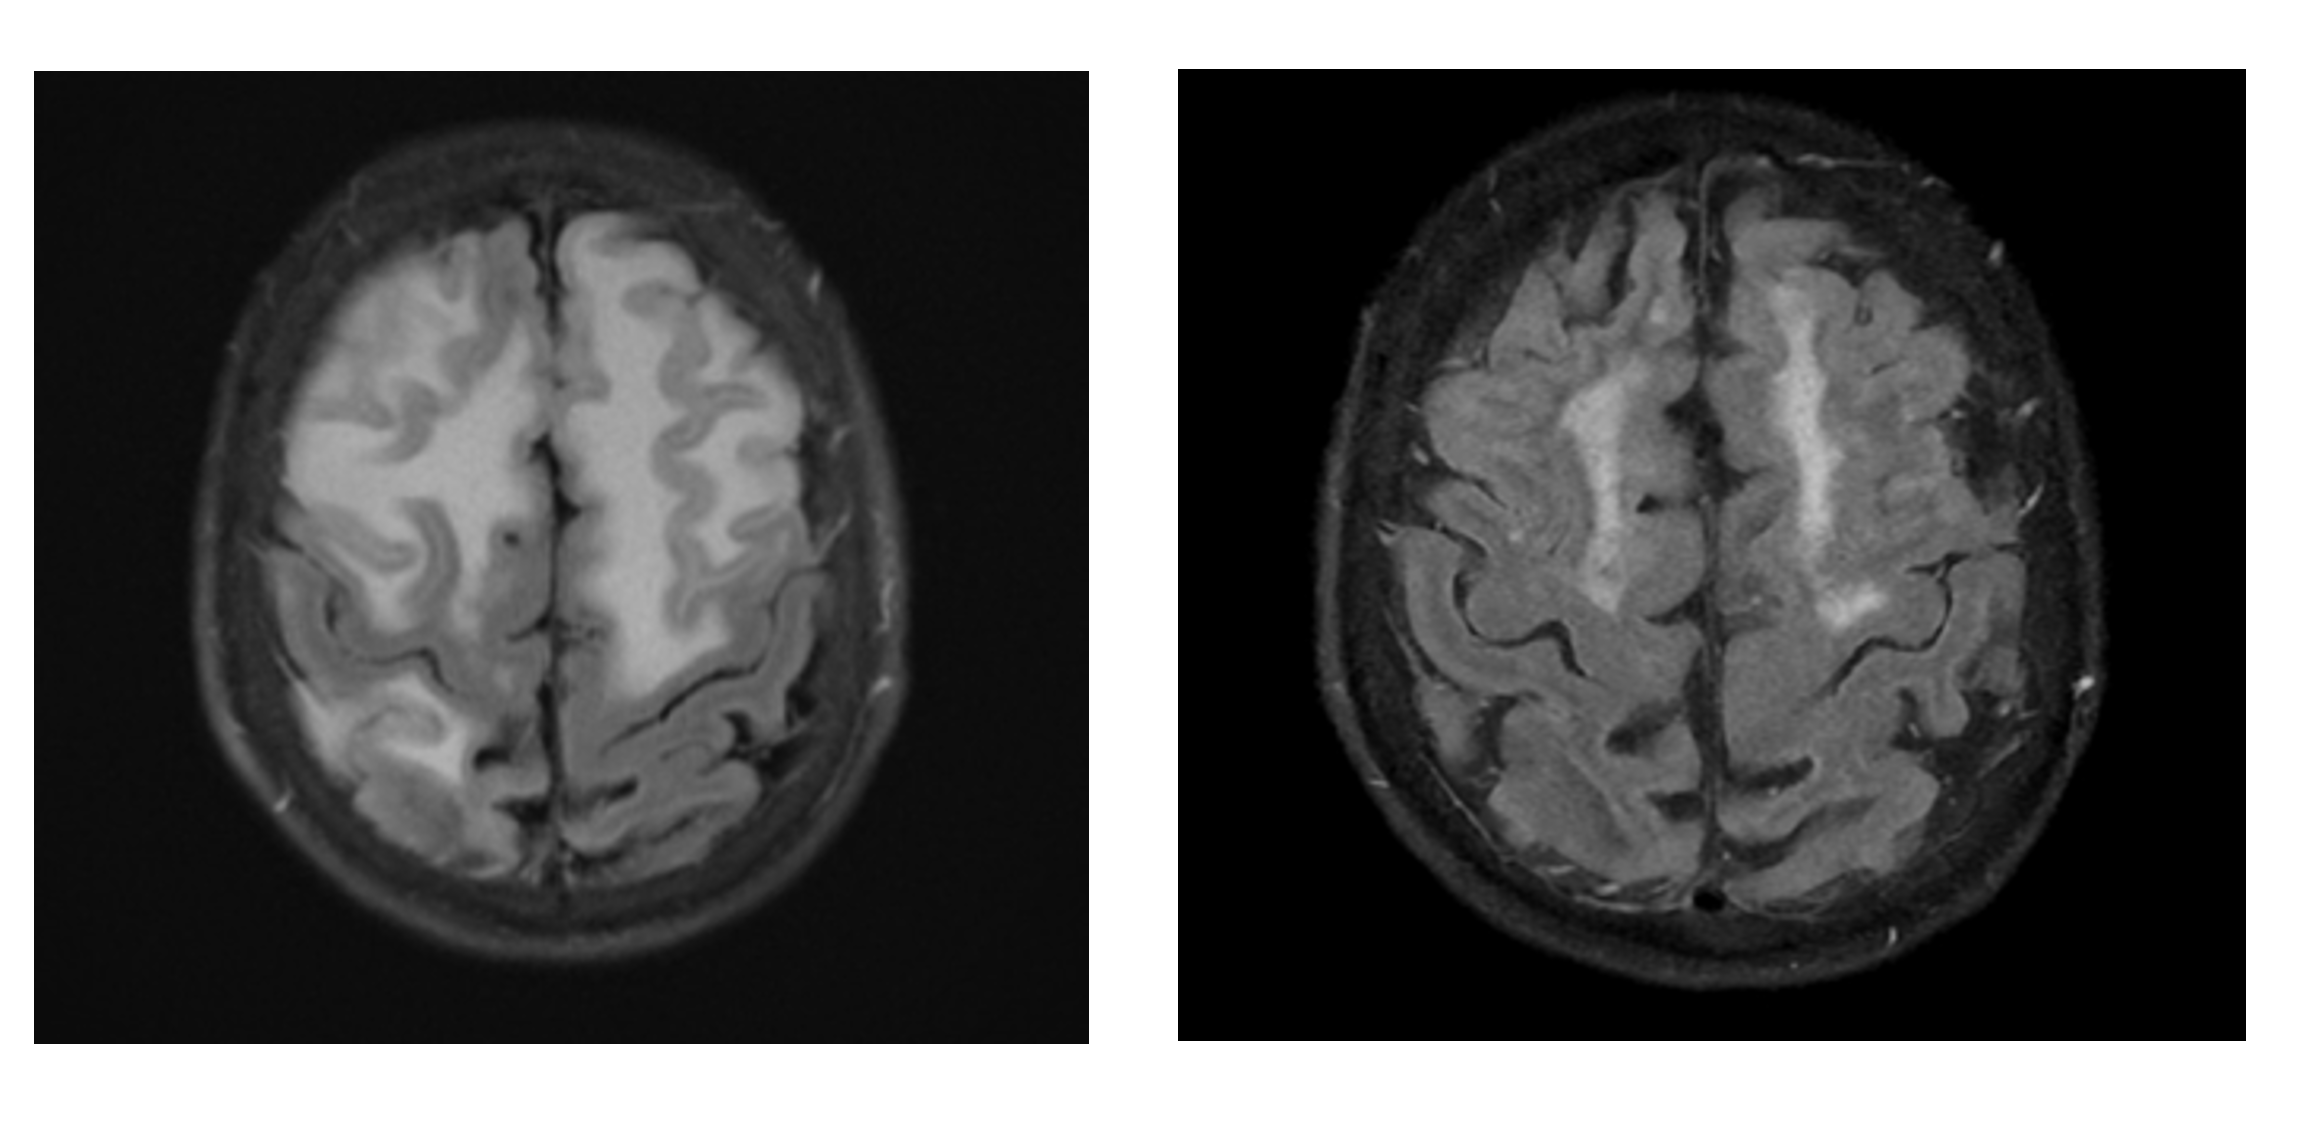

Case Report: Inflammatory Cerebral Amyloid Angiopathy - Recognizing a Treatable Form of Cerebral Vasculitis

Garrett Harris1, Chimaobi Ochulo2, and Arjun Athreya1